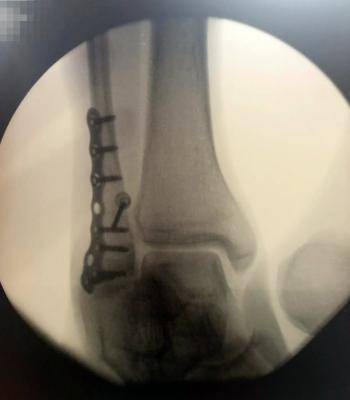

廖永谊昨早受访时说,手术很顺利,他与记者分享手术后的X光片,只见锁上七个大螺丝,令人触目惊心。

廖永谊的X光片,清楚可见锁上七个大螺丝。